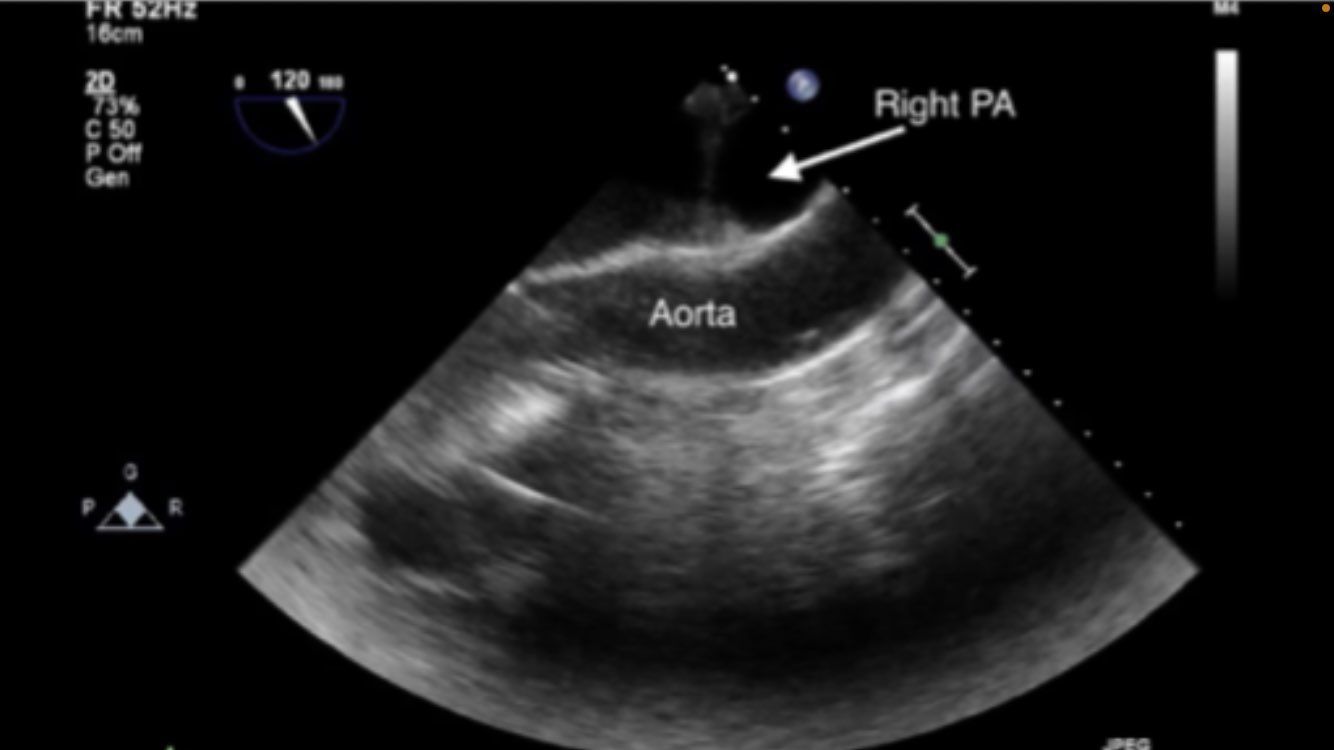

Midesophageal ascending aortic short axis SAX

Mid esophageal RV inflow and outflow